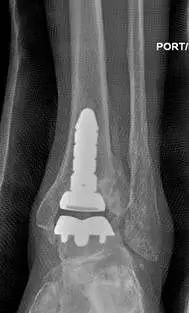

The following are images after surgical replacement of the ankle joint with a mobile bearing ankle prosthetic called the S.T.A.R. (SBI). This replacement joint will function similarly to a normal anatomical joint, allowing the patient normal function in daily activities, but was not designed to take repetitive use during more intense athletic activity. The joint has a polyethylene spacer between two metal parts that acts as shock absorber and gliding agent similar to cartilage. There is physical therapy that is required after surgical joint replacement in order to get the patient back to funcional capacity.

Post-traumatic arthrirtis treated with Total Ankle Replacement